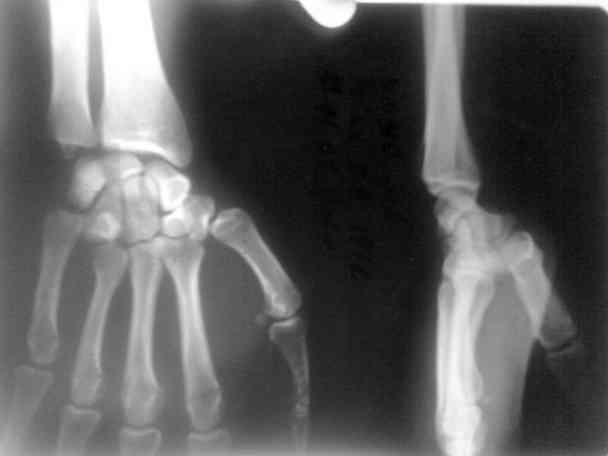

Дорогие коллеги,предлагаю посмотреть интересный случай. больной лечился в гипсовой лонгете 15 дней как ушиб.

правильный диагноз не был установлен.

я случайно взял эти снимки и посмотрел

поставил диагноз вывих 5 пястной кости.

больного я направил в область. его прооперировали. вынесены снимки.посмотрите.

Свежие вывихи 5 пястной или 4-5 пястных костей легко устраняются и могут вестись консервативно в гипсовой лангете. В представленном случае, через 15 дней после травмы, все сделано грамотно. Кстати, такие вывихи встречаются не совсем редко.